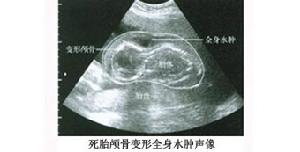

2、超聲檢查:胎兒死亡時間不同,其超聲檢查顯像亦不同。死亡時間較短,僅見胎心搏動消失胎兒體內各器官血流臍帶血流停止身體張力及骨骼、皮下組織回聲正常,羊水無回聲區無異常改變。死亡時間較長超聲反映的胎兒浸軟現象與放射學影像相似,顯示胎兒顱骨強回聲環形變顱骨重疊變形;胎兒皮下液體積聚造成頭皮水腫和全身水腫表現;液體積聚在漿膜腔如胸腔、腹腔;腹腔內腸管擴張並可見不規則的強回聲顯示;少量氣體積聚也可能不產生聲像陰影。如果死胎稽留宮內,進一步浸軟變形,其輪廓變得模糊,可能會難以辨認,此時須謹防孕婦彌散性血管內凝血(DIC)的發生。偶爾超聲檢查也可發現胎兒的死因如多發畸形等